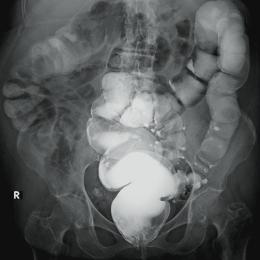

Hémorragies digestives

Les hémorragies digestives sont un motif fréquent de recours aux soins, toutefois les présentations, les localisations, les causes et les niveaux de gravité sont très variés. L’urgentiste et le réanimateur sont au cœur de la prise en charge initiale, avant d’être épaulés, et souvent…